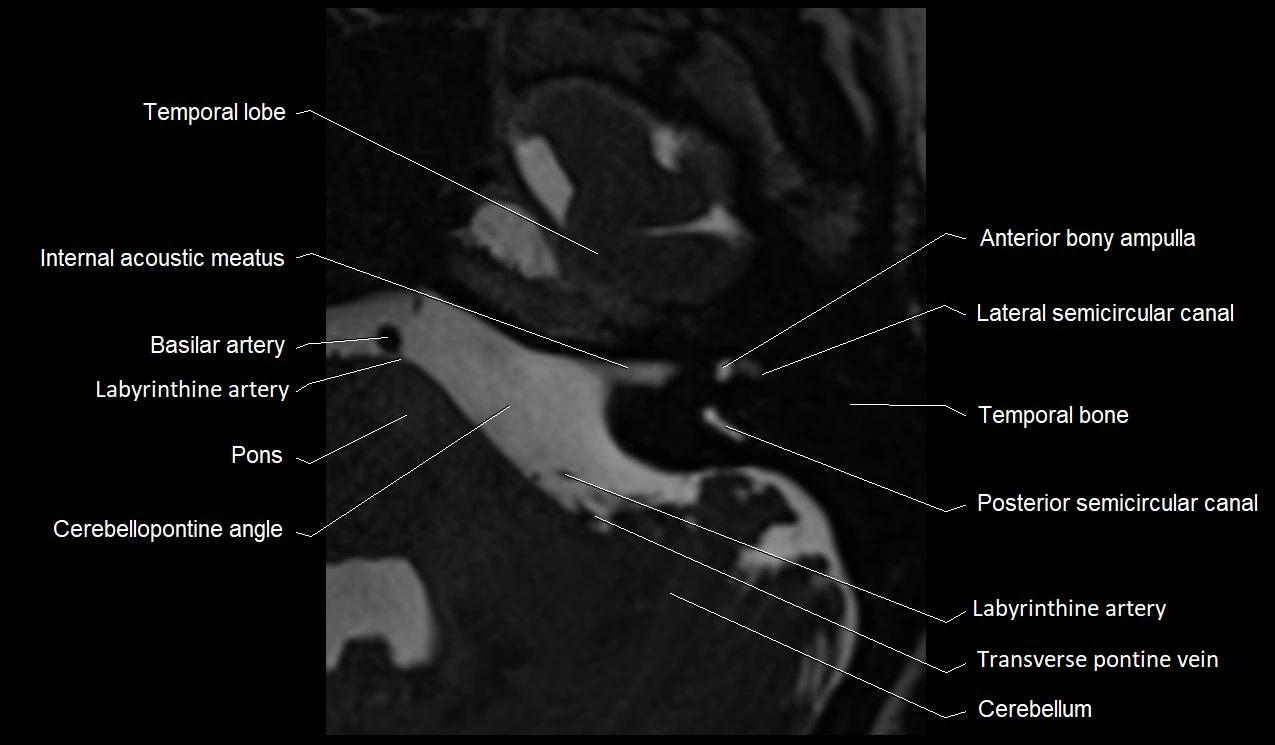

MRI images

image